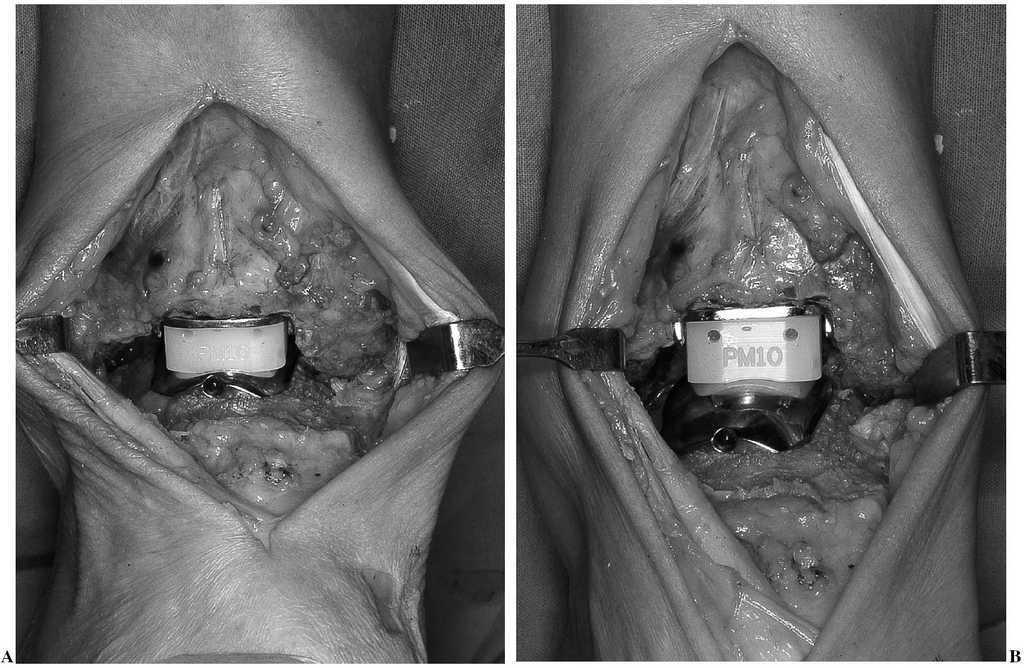

Figura 4. Introducción del componente intermedio móvil. Los componentes tibial y astragalino ya han sido implantados.

Figura 5. Prótesis total implantada. (A) flexión dorsal. (B) flexión plantar. Obsérvese el deslizamiento de la pieza intermedia.